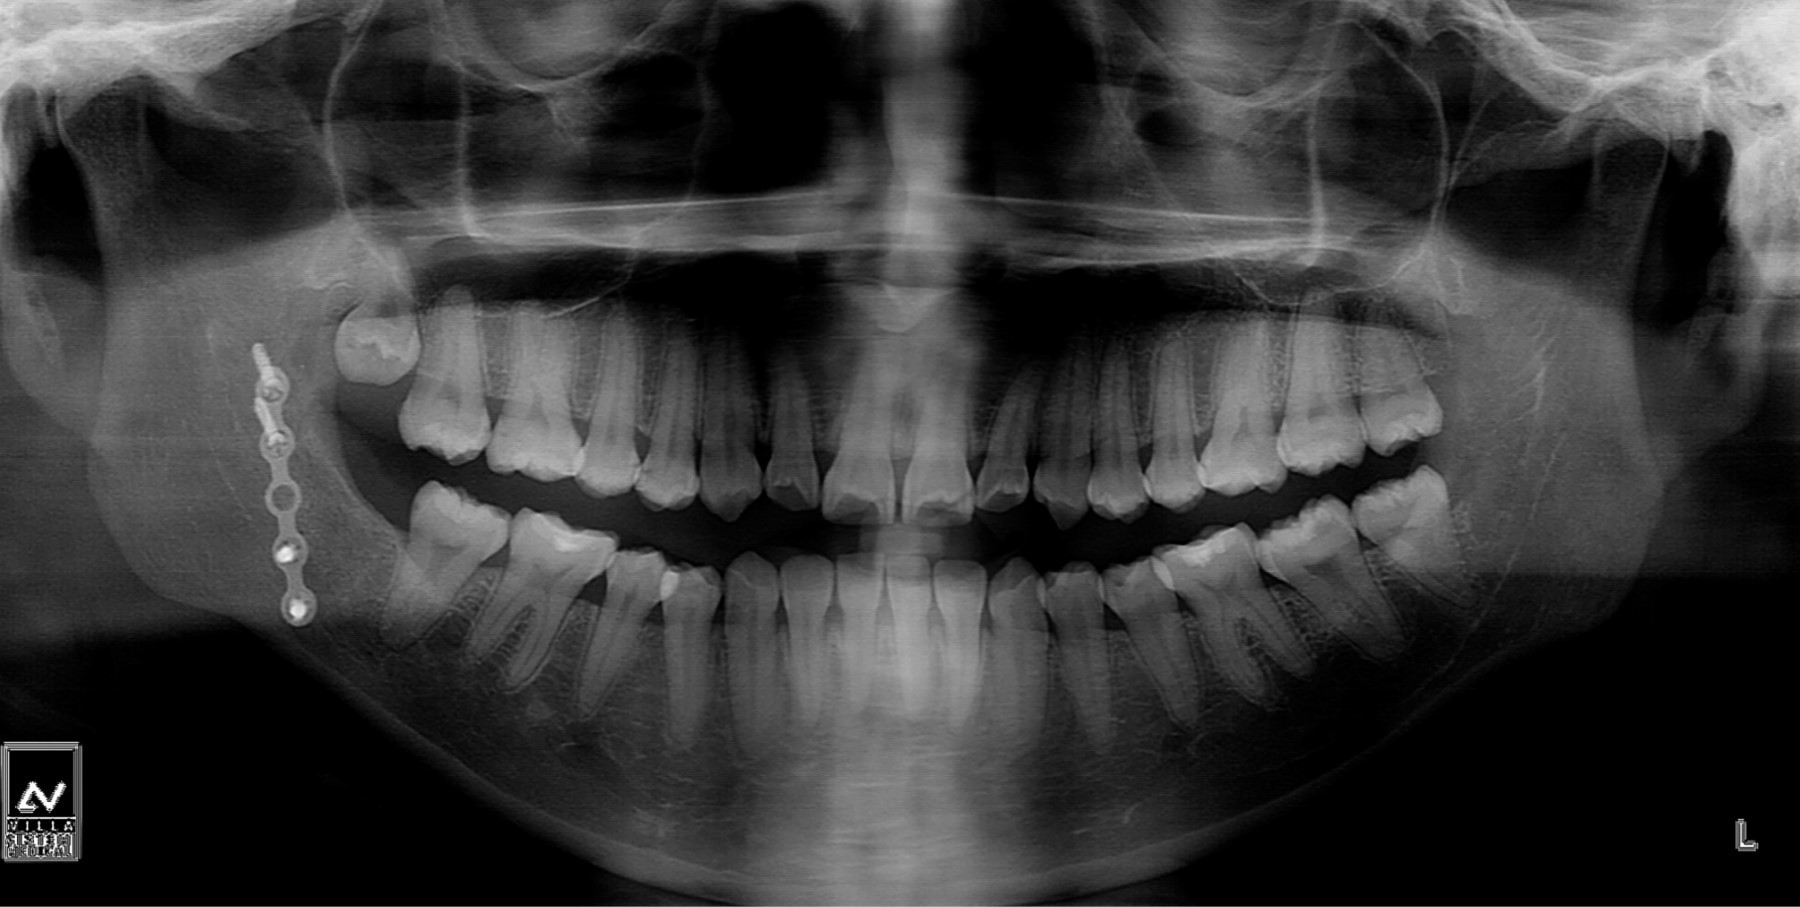

Dentro de los hallazgos imagenológicos se encontró imagen hiperdensa de forma fusiforme, de densidad similar al metal, de una longitud de 2.6 cm y un diámetro de 2 mm, esta misma se localizaba en la FP derecha, al correlacionar con el antecedente quirúrgico este CE era compatible con un fragmento de una broca percutánea del sistema 2.0; también se observan imágenes hiperdensas compatibles con una miniplaca de osteosíntesis con cuatro tornillos en ángulo mandibular, así como un área hipodensa correspondiente al trazo de fractura en proceso de cicatrización (Figuras 1 y 2).

Se realizó el retiro del CE mediante el fluoroscopio en sala de operaciones con un abordaje mínimamente invasivo en fondo de vestíbulo, pudiendo encontrar y remover exitosamente el CE de la FP derecha (Figuras 4 y 5). Posteriormente, se trató a la paciente mediante una férula miorrelajante, acompañada de fisioterapia por un lapso de cuatro meses, logrando así la recuperación de la apertura bucal, 35 milímetros aproximadamente (Figura 6). Es importante mencionar que entre el CE y los tejidos blandos circundantes se formó un área de tejido fibroso, la cual estaba condicionando la limitación de la apertura bucal. Se tomaron radiografías de control, las cuales evidenciaron la correcta consolidación de la fractura de ángulo derecho (Figura 7). Finalmente, la paciente fue transferida a ortodoncia para realizarse el tratamiento ortoquirúrgico de la maloclusión clase III.